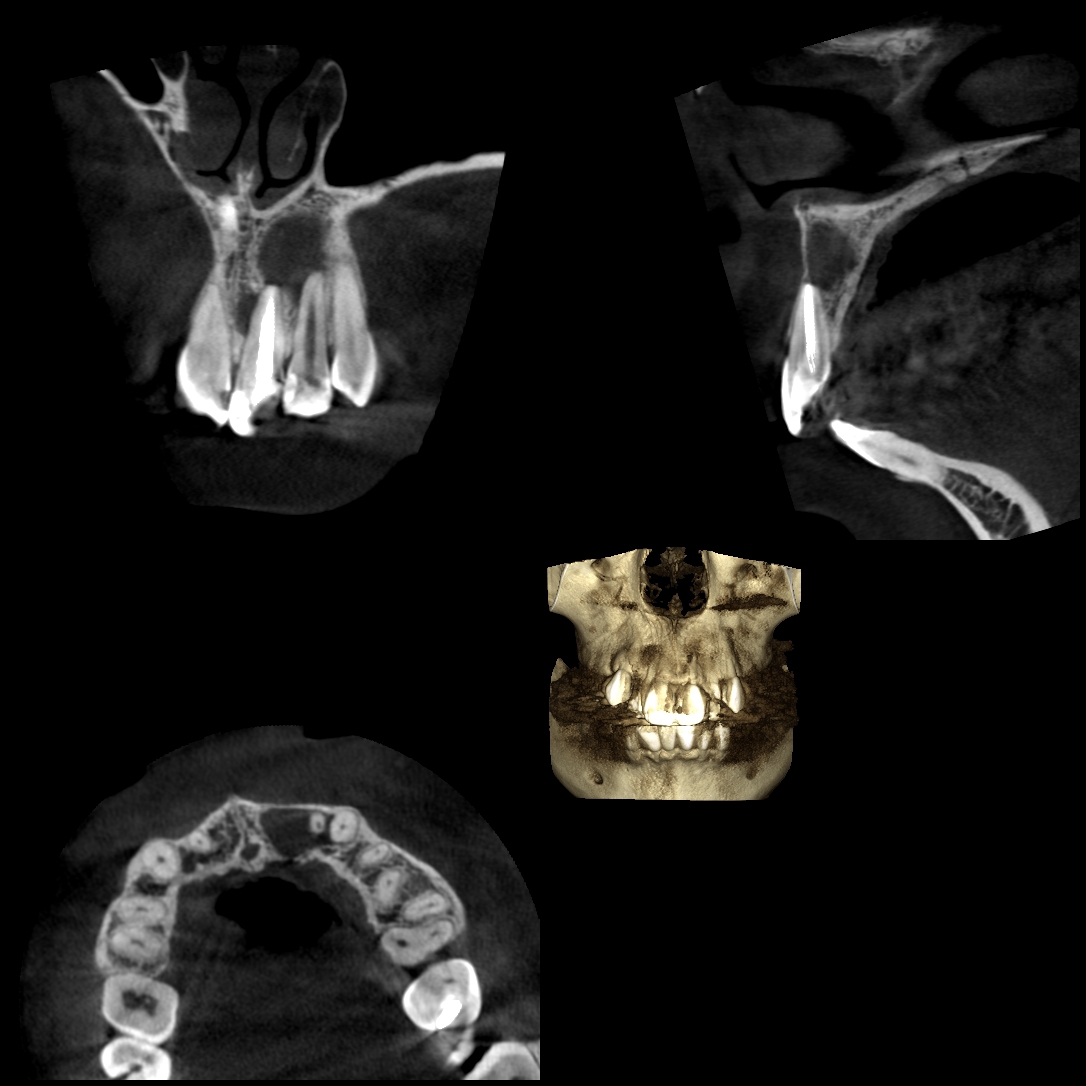

根管治療とCT

根管治療とは、歯の神経を取ったり、根の中をお掃除する治療です。CT画像では、根の本数や神経の入っている管の方向・位置がわかります。また、根の先端にある病巣の確認・位置・大きさを立体的に確認することができ、治療後の治り具合などをかなり正確に把握することができます。